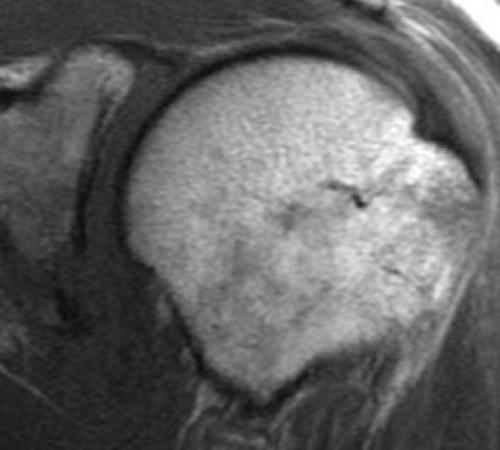

Разрыв вращательной манжеты – также характерное повреждение области плеча – может быть связан как с травмой, так и дегенеративными процессами. Разрывы вращательной манжеты бывают полные и неполные. Кроме того, по МРТ плечевого сустава выделяют 3 градации, в основе которых лежит не только изменение сигнала на Т2-зависимых томограммах, но и морфологические изменения сухожилия.

МРТ. Корональная Т2-зависимая томограмма с подавлением сигнала от жира. Полный разрыв сухожилия надостной мышцы.